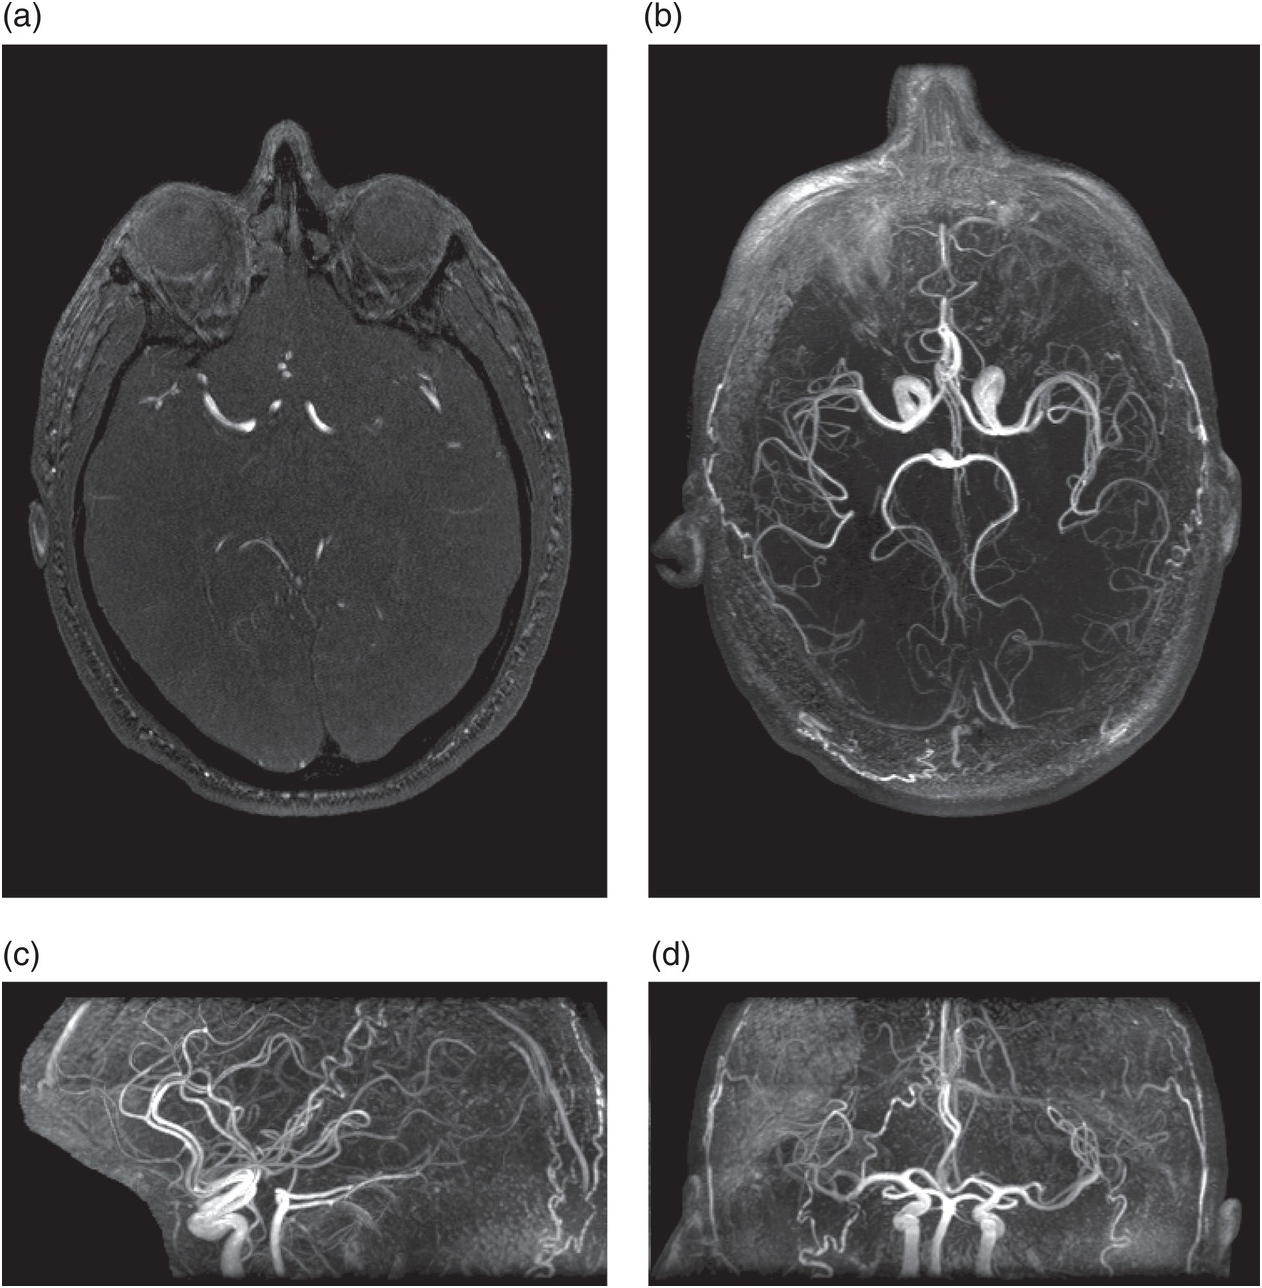

Chụp cộng hưởng từ hệ mạch máu nội sọ tiêm thuốc đối quang từ là kỹ thuật sử dụng từ trường và các xung năng lượng sóng vô tuyến đồng thời sử dụng thuốc đối quang từ đường tĩnh mạch nhằm mục đích khảo sát hệ mạch cảnh - sống nền nội sọ hiệu quả. Phương pháp này cho phép thăm khám cả hệ động mạch và hệ tĩnh mạch não, có khả năng phát hiện được nhiều bệnh lý mạch máu não như hẹp mạch, dị dạng động tĩnh mạch, phình mạch, dị dạng tĩnh mạch Não hay các huyết khối động mạch cũng như tĩnh mạch.

Kỹ thuật này là 1 kỹ thuật khảo sát hệ mạch cảnh sống nền và nội sọ hiệu quả, độ chính xác cao hơn so với thăm khám hệ mạch máu não bằng cộng hưởng từ không tiêm thuốc đối quang từ. Tuy nhiên có thể xảy ra các tai biến liên quan đến thuốc đối quang từ.

- Bác sĩ nghi ngờ bệnh nhân mắc các bệnh lý mạch máu nội sọ như:: dị dạng mạch máu não (động mạch hoặc tĩnh mạch), chứng phình động mạch, hẹp mạch não trong và ngoài sọ;

- Đột quỵ não: Nhồi máu não tìm vị trí tắc mạch lớn, Xuất huyết não mà cần tìm phình mạch, dị dạng mạch, dò động mạch cảnh - xoang hang...;